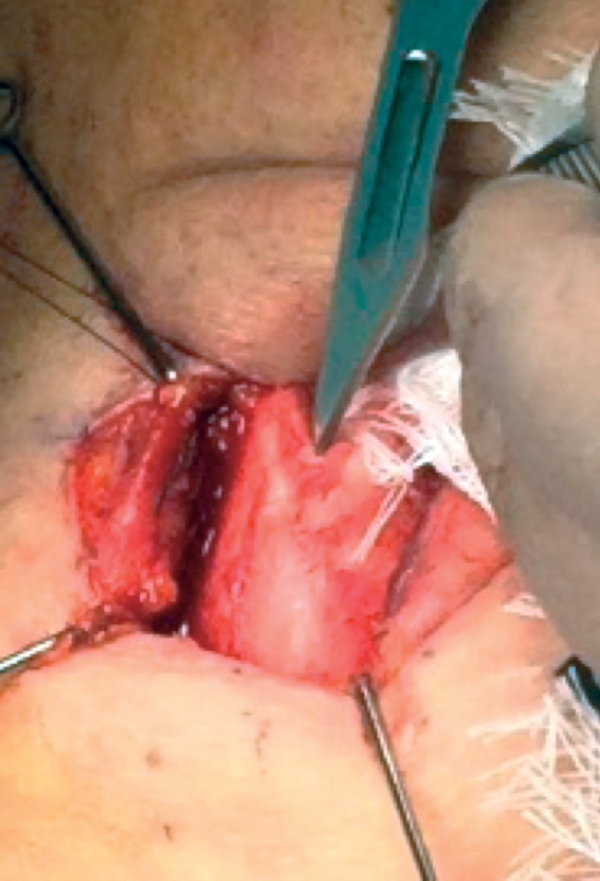

Separation of thyroid lamina with a frying-pan otology knife

Complete the cartilage separation using an otological frying pan knife. The inner perichondrium must not be penetrated otherwise there is risk of surgical emphysema. It is best to leave a thin layer of cartilage and use the spreader to separate it. Warning; a tear of the inner perichondrium is worse if perforation is in the subglottic area because of the high subglottic pressure. This must be repaired by inserting a small muscle flap and Tisseel. Beware, do not repair with stitches otherwise the perforation will only get bigger! There is no perichondrium here as the vocal cords are directly attached to the thyroid cartilage at this level.